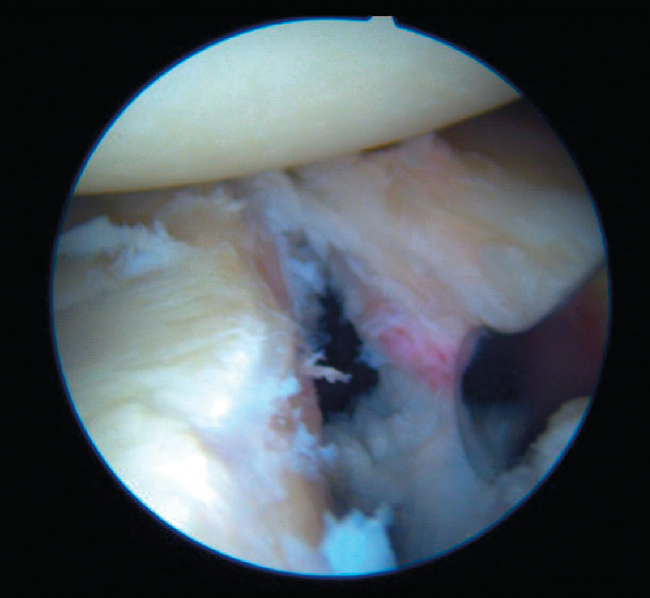

Bankart lesion consists of deinsertion of the glenohumeral ligaments and labrum in its anteroinferior portion. It is the most common type of lesion in cases of anterior instability and is moreover present after a first luxation episode in 90% of all traumatic dislocations. Instability is usually a consequence of failure of these lesions to heal, or of healing in an anomalous position, usually in the form of medialization over the neck of the glenoid cavity.

Arthroscopic Bankart repair is regarded as the first option for the treatment of traumatic, unidirectional, anteroinferior and inferior instability of the shoulder. Surgical treatment involves labrum release and mobilization, allowing it to be reinserted in its correct position. Such release and correction of the position of the labrum proves technically more complex in ALPSA (anterior labroligamentous periosteal sleeve avulsion) and Perthes type lesions, but is essential in order to ensure effective repair of the labrum. In this way, Bankart repair affixes the labrum to the margin of the glenoid cavity and ascends the capsule and ligaments proximally, providing them with tension.

The patient may be placed in a deck chair or in lateral decubitus, depending on the preference of the surgeon. We start by inserting a 30º arthroscope through a standard vision posterior port. Systematic exploration of the glenohumeral joint is very important for establishing a firm diagnosis of all the lesions, evaluating possible detachments of the anterior labrum, capsular tears, upper labral lesions and biceps lesions, bone damage including Bankart bone lesions and HSLs, rotator cuff disease and alterations of the inferior part of the capsular recess in order to discard humeral avulsion of the inferior glenohumeral ligament.